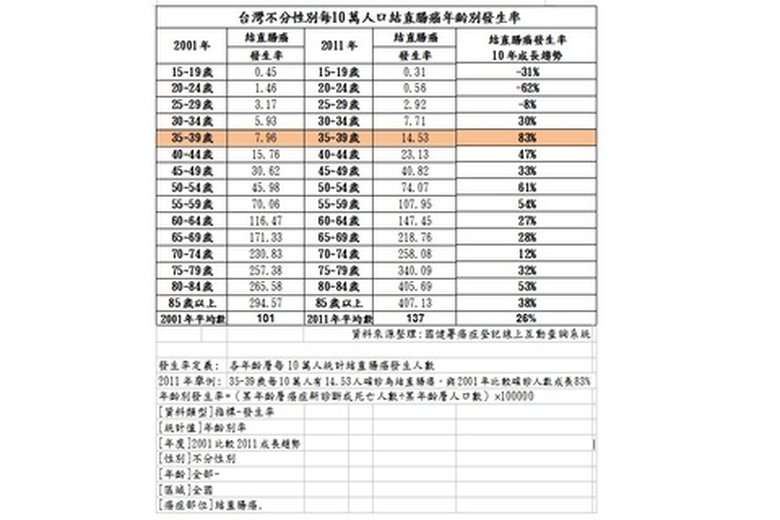

國民健康署2011年最新癌症統計,男女性大腸癌發生率多在40歲以後,大腸癌在55-64歲年齡層為發病高峰,原因是飲食西化,外食比率高、多油、多肉、低纖維的食物。大腸癌在零期或一期的治療研究顯示,存活率可以高達百分之80以上。定期大腸鏡檢查是預防大腸癌的不二法門。